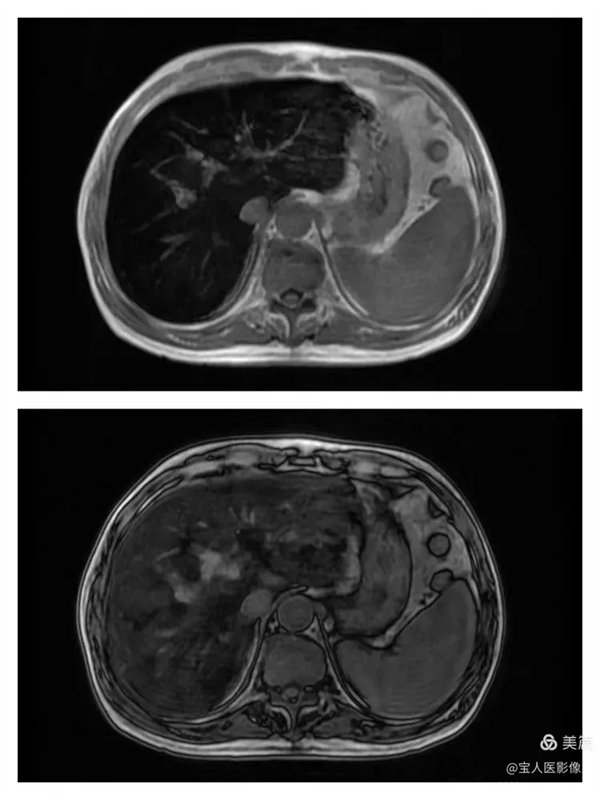

T1WI圖,軸位,肝實質信號仍呈明顯低信號。

同、反相位,肝實質信號反相位略不均勻升高。